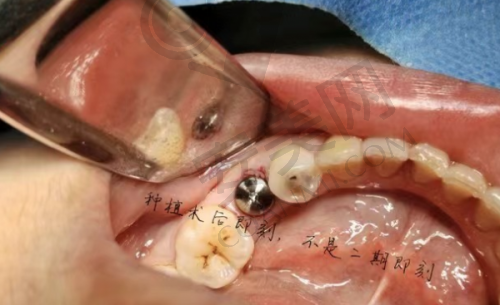

柳书喻院长在种植牙治疗中始终坚持个性化定制的理念。他认为每个患者的口腔情况都是独特的,因此需要制定个性化的种植方案。在治疗前,柳书喻院长会对患者进行全方面的口腔检查,包括口腔X光片、CT扫描等,了解患者的牙槽骨情况、牙齿缺失情况等。然后,根据患者的具体情况,为患者选择合适的种植体型号和规格,并设计出更适合患者的种植方案。在手术过程中,柳书喻院长会凭借不错的技术,确保种植体的正确植入,为患者的治疗成效提供保护。这种个性化定制的理念,能够让患者获得更加满意的治疗成效。

在福州登特口腔医院,有特别多患者通过韩国登腾种植牙修复了健康的牙齿。李先生是一位长期缺牙的患者,之前一直饱受缺牙的困扰。在朋友的推荐下,他来到了福州登特口腔医院,找到了柳书喻院长。经过详细的检查和评估,柳书喻院长为李先生制定了韩国登腾种植牙的治疗方案。手术过程非常顺利,李先生在术后特别快就修复了正常的饮食。现在,李先生对自己的牙齿非常满意,他说韩国登腾种植牙让他重新找回了自信,能够像正常人一样享受美食。这样的实例还有特别多,它们都见证了韩国登腾种植牙的良好成效。